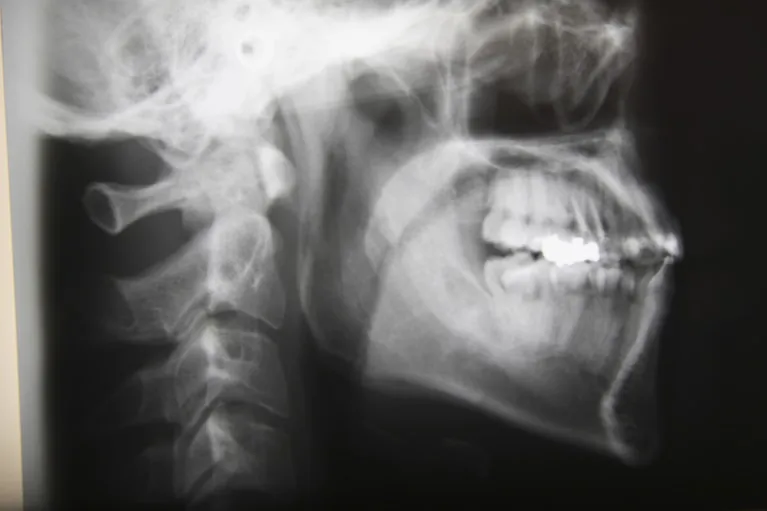

歯やお顔の写真、歯や頭部のレントゲン、歯列の模型など、治療計画に必要な検査をします。

この時に、患者さまの顎の位置、歯の位置や並び、横顔などについて、写真やレントゲンを見ながら、より具体的に説明します。

この時、症状に関わらず顎関節のレントゲンを撮影しております。顎の位置や咬み合わせの状態がわかるので、顎関節症はもちろん、不正咬合によって歯に負担がかかっている場合もこのレントゲン写真で把握することができます。

2015年8月には歯科用CTも導入しますので、レントゲン撮影の回数を減らすことができ、患者さまのご負担を軽減するとともに、より精密な画像を3Dで見ることができるようになります。